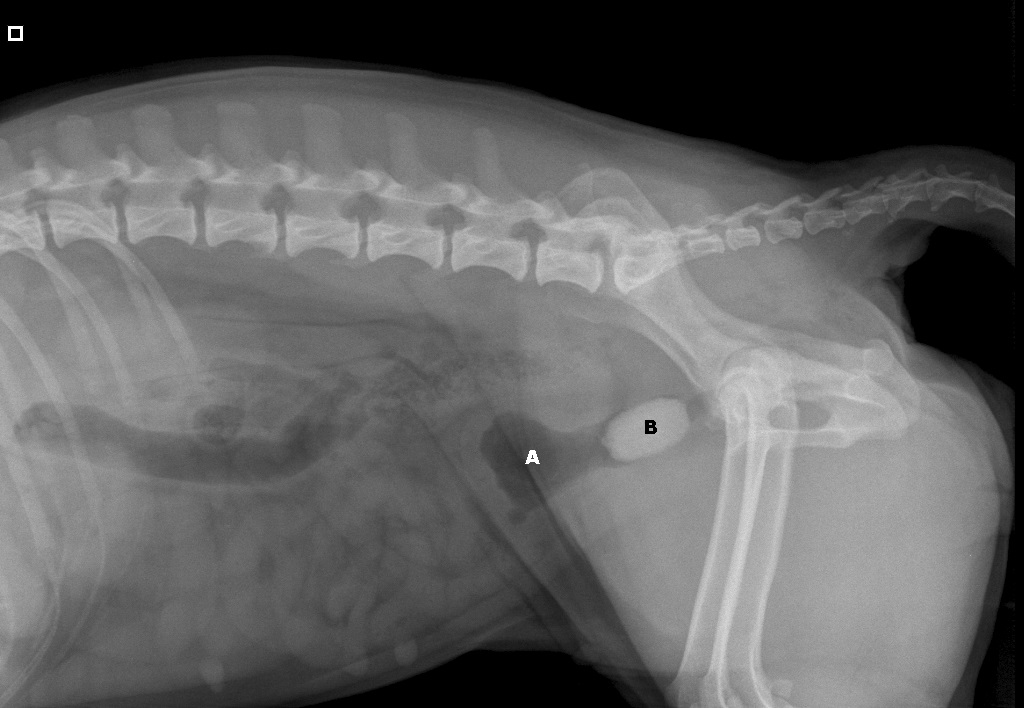

Röntgenfoto van Yvi:

A: blaas

B: de steen

De blaas heeft een erg dikke wand (witte cirkels)

en de steen sluit de uitgang van de blaas volledig af (rode cirkel)